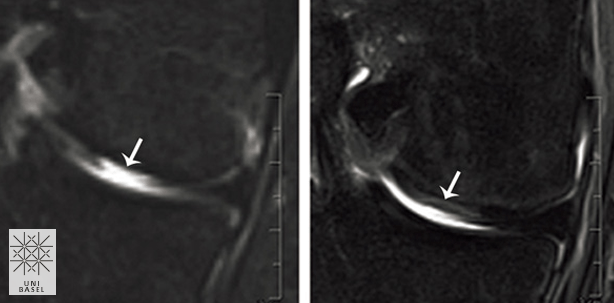

Die Knorpelzellen der Nasenscheidewand (nasale Chondrozyten) haben die besondere Fähigkeit, sich zu regenerieren. Für eine laufende klinische Studie entnahmen die Forschenden bisher bei sieben von insgesamt 25 unter 55-jährigen Patienten kleine Biopsien von 6 Millimeter Durchmesser aus der Nasenscheidewand und isolierte daraus die Knorpelzellen. Diese vermehrten sie in Kultur auf ein Vielfaches der ursprünglichen Zellzahl und brachten sie danach auf ein Gerüst auf, um ein Knorpelstück von rund 30 x 40 Millimeter Grösse zu züchten. Einige Wochen später entfernten sie das beschädigte Knorpelgewebe am Knie der Patienten und ersetzten es durch das herangewachsene und zugeschnittene Gewebe aus der Nase. Mit demselben Verfahren haben die Forschenden in Basel bereits in einer klinischen Studie, in Zusammenarbeit mit der plastischen Chirurgie, kürzlich Nasenflügel rekonstruiert, die von Tumoren befallen waren.

„Die Erkenntnisse aus der Grundlagenforschung und den präklinischen Studien über die Eigenschaften der Nasenknorpelzellen und den daraus gezüchteten Transplantaten haben die Möglichkeit eröffnet, eine innovative Behandlung für Knorpeldefekte bei Patienten zu untersuchen“, sagt Prof. Ivan Martin zu den Studienergebnissen. Bereits früher wurde gezeigt, dass die Fähigkeit der menschlichen Nasenknorpelzellen, zu wachsen und neue Knorpel zu bilden, kaum altersabhängig ist. Deshalb könnten auch ältere Menschen von der neuen Methode profitieren, ebenso Patienten mit grösseren Knorpelverletzungen. In der laufenden klinischen Studie mit 25 Patienten am Universitätsspital Basel wird weiter untersucht, wie mit Knorpelzellen aus der Nasenscheidewand gezüchtete Knorpelgewebe sicher und ohne Nebenwirkungen in Gelenke transplantiert werden können.